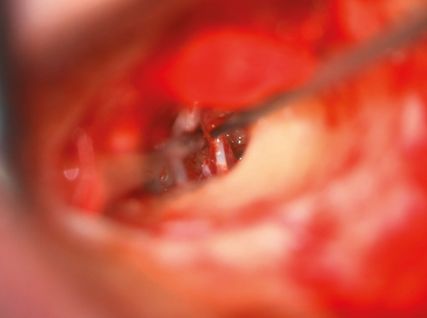

Abb. 3: Nach Entfernung der Stapessuprastruktur Perforation der Stapesfußplatte mit dem Laser

Die Therapie der Wahl stellt die operative Sanierung durch die Stapesplastik dar. Dabei wird der versteifte Stapes durch eine Protheseersetzt, die durch die perforierte oder teilentfernte Stapesfußplatte ins Innenohr ragt und am Incus fixiert wird. Im Laufe der Zeit haben sich Variationen der Operationstechnik ergeben und verschiedene Prothesenformen wurdenentwickelt. Die Wahl des Vorgehens und der Prothese hängt maßgeblich von den Vorlieben und der Praxis des Operateurs ab.10

In den Abbildungen 2–4 sind die Operationsschritte, wie sie in der Regel in unserer Klinik erfolgen, dargestellt.